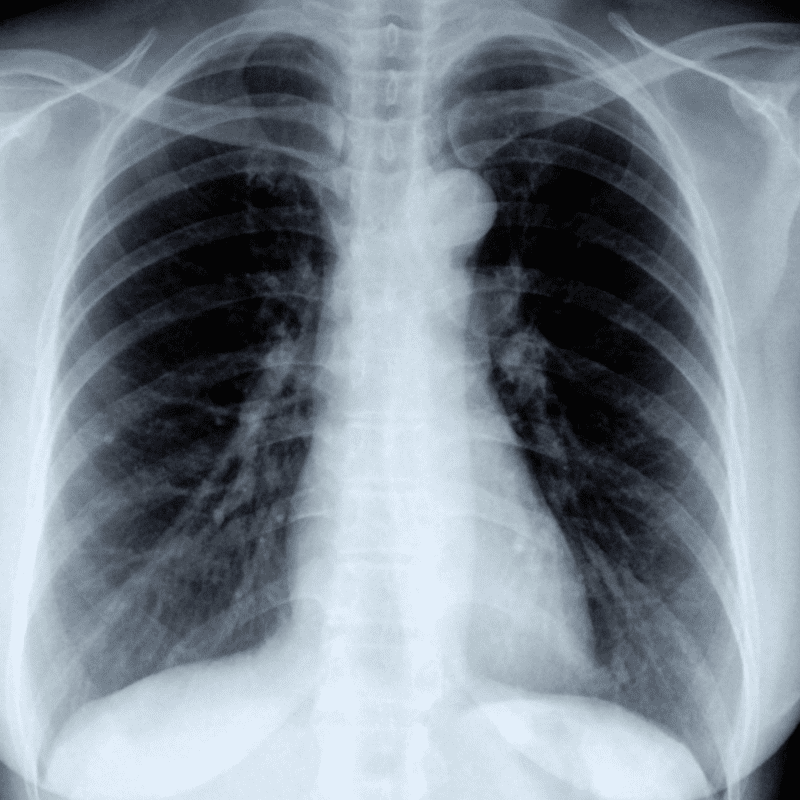

It consists of various tests, such as full blood count, liver function tests, lipid profile, thyroid stimulating hormone, and screenings for hepatitis B, HIV, and syphilis. The package also includes a pap smear, ECG, and USG breast with specialist reporting.

These advanced ultrasounds are utilised for various purposes, including antenatal scans as well as assessments of organs such as the liver, kidneys, gallbladder, spleen, bladder, uterus, and ovaries.